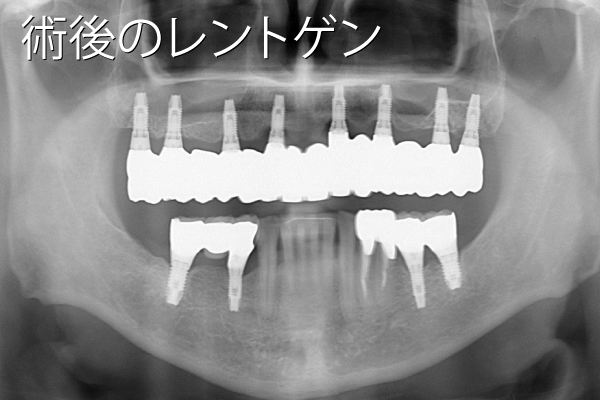

- 性別年齢

- 男性:55歳

- 治療内容

- 上顎に8本、下顎に6本のインプラント治療

- 金額

- 770万円(税込)

- 来院理由

- 歯周病が進行してきて噛めないし、口臭もひどい。専門医にインプラント治療について相談したい。

- 施術の

副作用

(リスク) - 経過とともになくなりますが、術直後に腫れや違和感を感じることがあります。